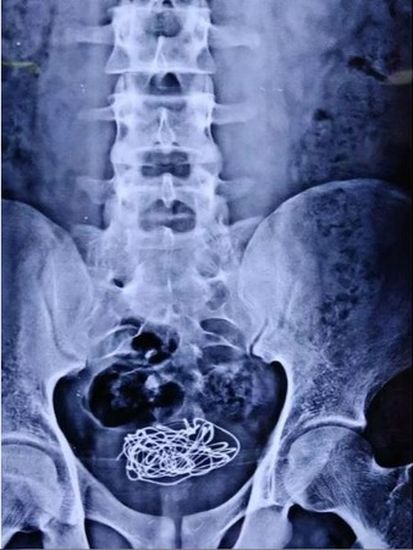

印度北方邦一名18歲少年最近因為腹部劇痛、難以排尿而求助泌尿科,經過X光檢查後,發現他的膀胱內竟然塞了一團電線。

英國醫學雜誌所最近公佈一個非常奇怪的案例,一名不肯透露姓名的印度少年腹痛求助醫生,卻拒絕透露腹部劇痛前到底做了甚麼,醫生們自行研究了他的病史,發現到他過去曾經有過將異物塞入自己體內的行為。

經過X光檢查後,照片中清楚地顯示他膀胱內有一團纏繞的電線,而這條電線正是導致少年腹部劇痛的元凶。少年事後將「真相」透露,自己10天前在自慰時,為了追求刺激將電線從陰莖推入尿道,結束後卻拿不出來,尿道被電線卡住,排尿都相當痛苦,只好前來求助。

醫生決定以激光將電線切割成數小段,再利用內窺鏡將這些片段的電線慢慢取出。最後手術成功,少年亦在隔天出院。

該醫學雜誌稱,激光也是一種「高效、強大的工具」,可以用來分解材料並在內窺鏡下移除。另外,異物塞膀胱並非罕見,醫療人員過往從病人膀胱中取出過情趣玩具、電話線、電池、筆尖等等。